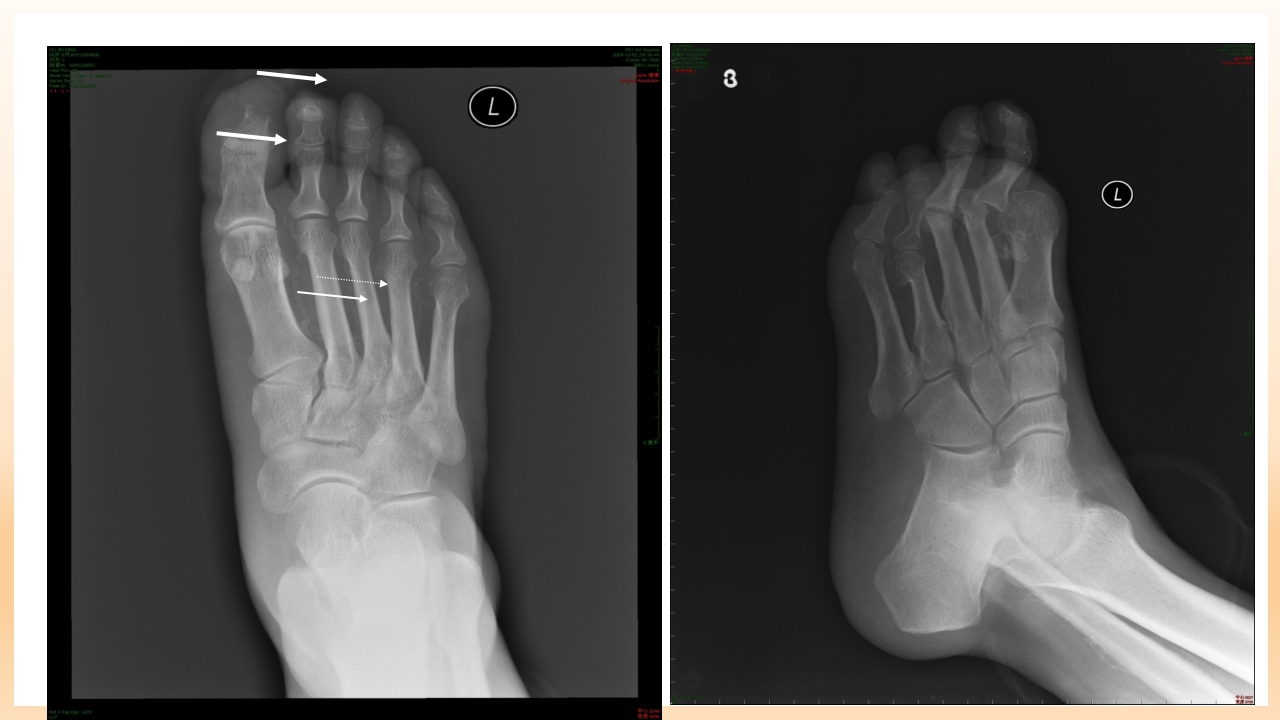

糖尿病足的治疗与护理 目录/content 一 糖尿病足的定义 二 糖尿病足发病机制及诊断? 三 糖尿病足如何治疗? 四 如何预防和护理糖尿尿足? 1 糖尿病足的定义 糖尿病足定义 糖尿病足:主要是与糖尿病下肢远端神经异常和不同程度的外 周血管病变相关的足部感染、溃疡和(或)深层组织破坏。 由于神经营养不良和外伤的共同作用,可引起Charot关节。 是糖尿病最严重的和治疗费用最高的慢性并发症之一。 糖尿病足流行病学资料 国外资料显示: 在所有因糖尿病住院的有关问题中,糖尿病足占到47%。 5%-10%糖尿病患者有不同程度足溃疡,1%的糖尿病患者截 肢。 糖尿病足是许多国家截肢首位原因。 中国糖尿病防治指南,2005,55 糖尿病足流行病学资料 在我国糖尿病足患病率占糖尿病患者的14%, ...